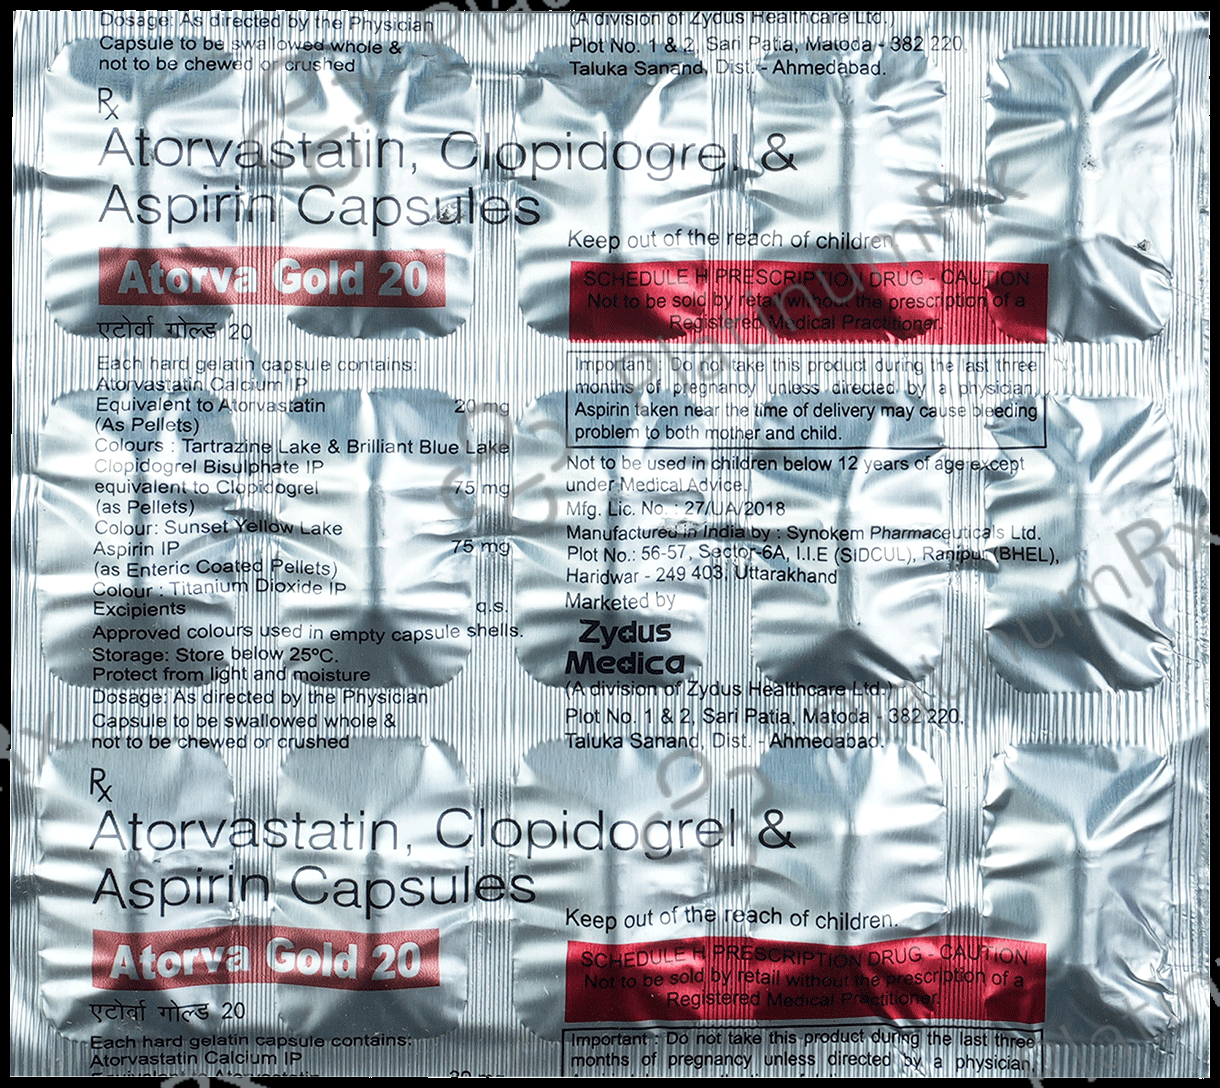

Aspirin 75mg + Atorvastatin 20mg + Clopidogrel 75mg

Salt CompositionAspirin 75mg + Atorvastatin 20mg + Clopidogrel 75mg (same for both)

Atorva Gold 20/75/75mg Capsule 15s

Atorva Gold 20/75/75mg Capsule 15s

Zydus Cadila

₹141.1